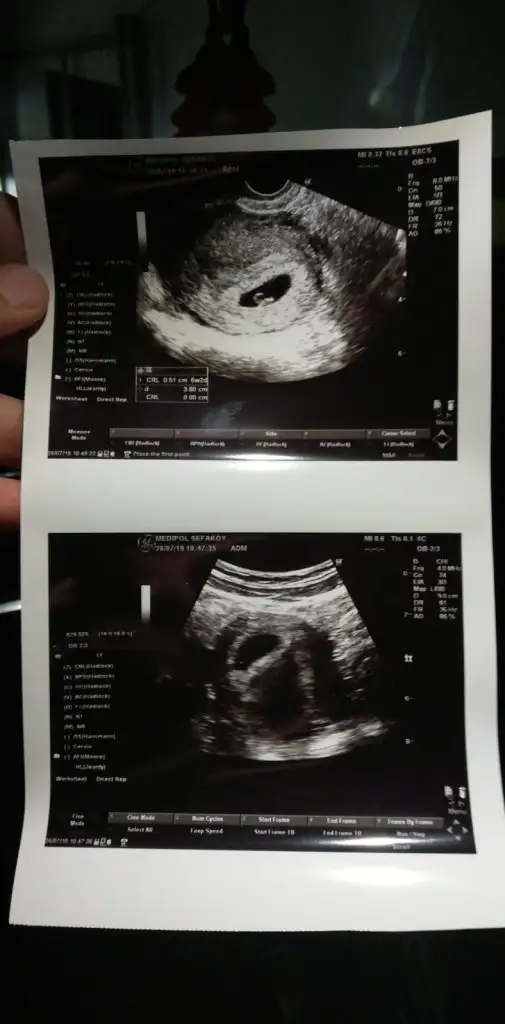

Ben göremedim usgKızlar beni de yorumlarmisiniz.Karindan ultrason 6 haftalik

6 Haftalık vajinal ultrason görüntüsü, ben de bir tahmin alayım lütfen :)

Evet karından usg fotoğrafı.Tesekkur ederimVajinalsa erkek karından usg ise kız